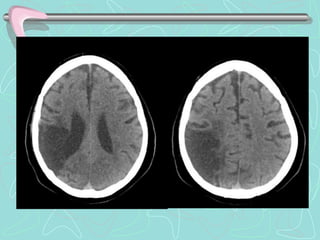

DIAGNÓSTICO

TOMOGRAFÍA COMPUTARIZADA DE ENCÉFALO

•Examen de elección en el Ictus agudo

ICTUS HEMORRÁGICO

•Lesión Hiperdensa que ocupa espacio y desplaza en

diverso grado el parénquima cerebral.

•En HSA puede ser poco hiperdensa, de ubicación

extraparenquimal, e invadir ventrículos cerebrales.

Las Neuroimágenes informan sobre el tipo de lesión, su

tamaño, localización, distribución vascular; la presencia de

complicaciones, y también sobre la necesidad de manejo

quirúrgico.